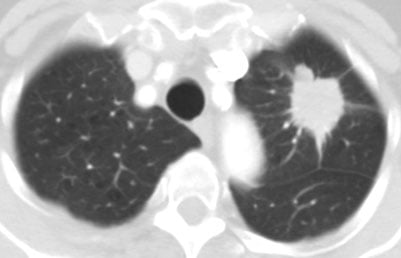

Lung Nodule and Lung Cancer Early Detection

It is well established that the larger the cancer, the worse the survival. Therefore, a systematic, organized evaluation of all newly discovered lung nodules is critical to improving outcomes. All incidentally discovered lung nodules deserve prompt evaluation since a significant number may be early-stage, and likely curable lung cancers.

The Lung Cancer Early Detection Center at Moffitt is specifically focused on evaluating patients with indeterminate (undiagnosed), newly-discovered lung nodules ranging from 6 mm-50 mm in size. The Lung Nodule Clinic is run by a thoracic surgeon along with our advanced practice professionals, where we use a standardized approach for patient evaluation including commercial diagnostic biomarkers, validated lung cancer risk algorithms and carefully follow the Fleischner Society and NCCN lung nodule management guidelines.